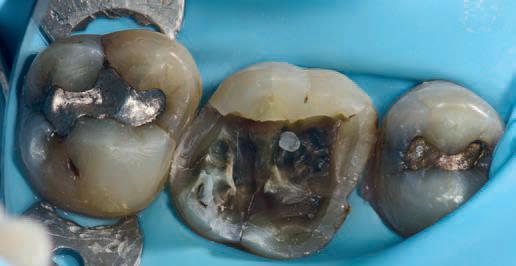

Clinical signs and symptoms

No teeth were tender to percussion. Tooth 26 reacted strongly to cold testing while the other teeth reacted normally. Tooth 26 tested positive to biting on damp gauze but the sensation did not linger. Both tooth 27 and 25 were negative to the bite test. The composite resin restoration in tooth 26 was removed under rubber dam and crack lines could be seen under the restoration (Fig. 1), with the most obvious running from the lingual to the centre of the tooth, and another from the mesiobuccal to the centre. A number of other minor cracks were visible, including one that ran under the buccal cusps (Fig. 1).

Fig. 1

In 2024, the patient presented again with pain in tooth 26. He reported the tooth was very sensitive to cold, with the pain lasting several minutes. He also reported that the tooth had ached spontaneously at times. On examination, the tooth reacted very strongly to cold, which lasted for almost one minute. The tooth was also slightly tender to percussion. The composite resin restoration appeared sound (Fig. 2). A PA radiograph (Fig. 3) revealed no PARL, but the pulp chamber was reduced in size when compared to a previous bite-wing radiograph.

Given the tooth’s previous history of visible cracks running into the tooth and the current symptoms of moderate to severe pulpitis, a decision was made after discussion with the patient to enter the pulp chamber to assess the condition of the pulp and the depth of the cracks. The plan was to either perform a full pulpotomy or, if no viable pulp tissue was present, extirpate the pulp.

Procedure and treatment

Using local anaesthetic and rubber dam isolation, access was obtained through the composite resin restoration. While the cracks were visible, they appeared similar to the image from 2018 (Fig. 4). The roof of the pulp chamber was removed and vital tissue was found, which did not appear to be heavily inflamed (Fig. 5). A pulp stone was also present (Fig. 6). Removing this revealed bleeding pulp tissue at the opening of the root canals. A cotton pellet soaked in NaOCl was placed on the pulp tissue at the opening of the root canal and after five minutes the bleeding had ceased (Figs. 7 and 8).

As the plan was to restore the tooth with a full- coverage indirect restoration, the entire pulp cavity was filled with Biodentinee™ with the Bio-Bulk Fill technique. (Fig. 9).

Fig. 2: Pre-op composite resin restoration, 2024.

Fig. 5: Initial exposure of the pulp chamber showing slight bleeding and pulp stone.

Fig. 3: PA radiograph.

Fig. 6: Pulp stone removed.

Fig. 8: Palatal root opening with vital tissue after bleeding has stopped.

Fig. 4: Initial access showing existing cracks.

Fig. 10: Tooth at 12-week review.

Fig. 7: Buccal root openings with vital tissue after bleeding has stopped.

Fig. 9: Cavity filled with Biodentinee™.

Discussion

This case highlights a number of elements of pulpotomies in teeth with cracks. Firstly, many teeth with deep cracks have a long-standing mild pulpitis, to which the pulp has responded by producing reparative dentinee that often appears in the form of a pulp calcification. The operator must be careful when performing vital pulp therapy on these teeth as it is often difficult to differentiate the pulp calcification from the floor of the pulp chamber.

Any pulp calcifications must be removed before assessing the condition of the radicular pulp tissue.

Secondly, in teeth with pulp symptoms resulting from cracks, it is best to perform a coronal pulpotomy. This allows the floor of the pulp chamber to be examined for any extension of the crack across the floor, which would greatly reduce the prognosis for the tooth.